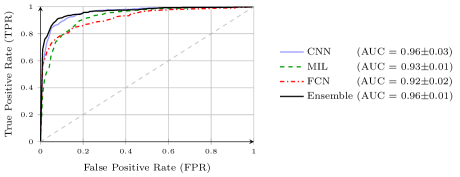

Pneumothorax is a critical condition that requires timely communication and immediate action. In order to prevent significant morbidity or patient death, early detection is crucial. For the task of pneumothorax detection, we study the characteristics of three different deep learning techniques: (i) convolutional neural networks, (ii) multiple-instance learning, and (iii) fully convolutional networks. We perform a five-fold cross-validation on a dataset consisting of 1003 chest X-ray images. ROC analysis yields AUCs of 0.96, 0.93, and 0.92 for the three methods, respectively. We review the classification and localization performance of these approaches as well as an ensemble of the three aforementioned techniques.

To increase the variability of the available data, we augmented the dataset by translating, scaling, rotating, horizontal flipping, windowing, and adding Poisson noise. Input images for CNN and FCN have been created by cropping a centered patch of from the original images resized to . For MIL we cropped overlapping patches out of the image resized to (cf. Fig. 2). In training, we used the Adam optimizer with default parameters and , a batch size of 16, and exponentially decreasing learning rate (LR). Refer to Table 1 for an overview of the parameters and to Fig. 4 for the receiver operating characteristic (ROC) analysis we performed to assess the model performance.

The pre-trained ResNet-50 was fine-tuned with an initial LR of for 40 epochs. For testing, an average five crop response of the model, i.e. center and all four corners, was used for the classification purpose. Very high and stable results can be reported, with area under curve (AUC) values of 0.960.03.

The pre-trained ResNet-50 was also employed as the patch-level classifier within the MIL approach. We chose the binary cross-entropy between the maximum patch score and the image-level label as the loss function. The batch size was selected as the number of patches per image. We trained with an initial LR of for 30 epochs and achieved an average AUC of 0.930.01 using this method. High patch scores (indicated by thicker red frames, cf. Fig. 5(c)) give a hint on the location of the pneumothorax.

As pixel-level ground truth annotations were available only for a subset of the images, 871 images in total were used for training the FCN for 400 epochs. As a loss function, a weighted cross entropy (25.0 for pneumothorax pixels and 0.5 for non-pneumothorax pixels in order to account for the smaller size of pneumothorax regions) was employed at pixel-level with an initial LR of . With an average AUC of 0.920.02, the overall performance of this method is worse than the CNN and MIL. On the other hand, the FCN generates pixel-level probabilities (cf. Fig. 5(d)), which indicate the location of the pneumothorax. The average Dice coefficient for positively classified cases is .

As can be seen from the previous sections, the different methods, that have been investigated, have their own advantages and disadvantages. However, looking at the performance, the errors made by different architectures do not necessarily coincide. Therefore, we investigated ensemble techniques, using linear combinations of the individual methods. The best parameter combination was identified using exhaustive search. The best ensemble of CNN, FCN, and MIL achieves the highest overall AUC of 0.965 (cf. Fig. 4), but does not significantly (at ) outperform the CNN. CNN and FCN achieve best results amongst combining two techniques with an AUC of 0.962.

Using the average AUC as a performance criterion, we achieved very stable results with values between 0.92 and 0.96 for all methods. These results indicate a very good overall performance of the algorithms.

The AUC provides little information about the performance in different areas of the ROC space. Particularly for the worklist prioritization, it could be argued that an operating point with a low false positive rate (FPR) is of most relevance. Even algorithms with a moderate true positive rate (TPR) could improve the clinical workflow compared to a sequential reading. In contrast, the reading of undetected pneumothorax cases could be delayed by already a small FPR. With respect to the overall performance of the individual methods, the CNN stands out, whereas the FCN allows for the detection of of all findings with false alarms, only exceeded by the ensemble with a TPR of .